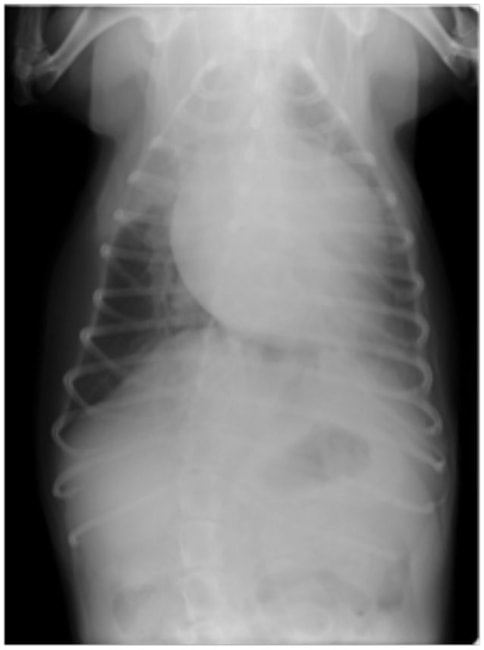

症例6:【ACVIM StageD ビーグル 10歳 去勢雄】

A:胸部レントゲン写真 側面像

B:胸部レントゲン写真 正面像

左側胸壁心尖部領域を最強点とするLevine 5/6の収縮期性心雑音が聴取された。安静時にも咳が認められる。胸部レントゲン検査において重度の心拡大が及び肺水腫が認められた。超音波検査では、重度の僧帽弁閉鎖不全、三尖弁閉鎖不全が認められた。三尖弁逆流速度から肺高血圧症が示唆された。ACE阻害薬、ピモベンダン、硝酸イソソルビド徐放剤、ベラプロストナトリウム、利尿剤としてフロセミド及びスピロノラクトンを用いて治療を行っている。